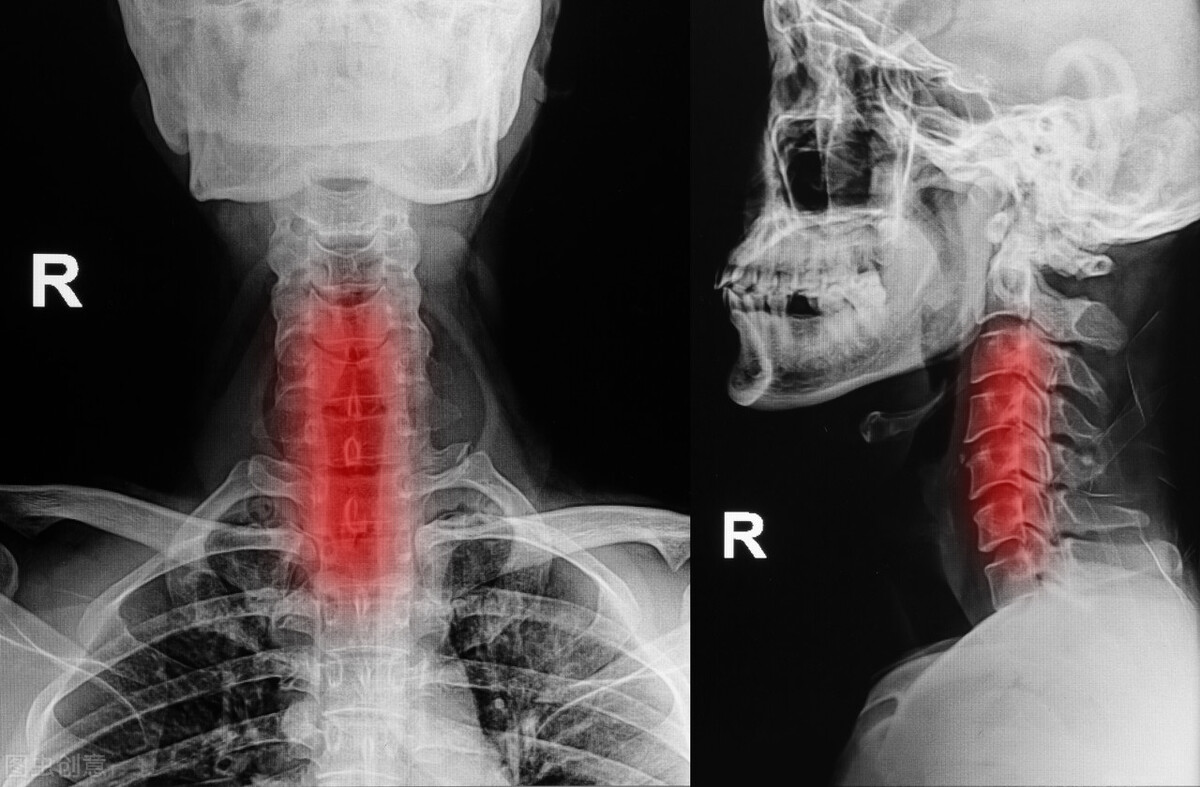

颈动脉位处心脏上方,血液是从下往上供血,这就不得不途径颈动脉了,因为这就是“古代所说的兵家必争之地”(唯一通道),一旦颈动脉发生了狭窄堵塞,血液就会因此供血减少,当这个堵塞严重到一定程度时,就会造成急性缺血性脑卒中,有死亡或瘫痪的可能。

颈椎虽然小,但作用极大,它连接了大脑和躯干,是大脑最主要的供血通道,同时其结构特殊,呈现Y字型,很容易出现动脉硬化,加速斑块血栓的形成。

当患者患有严重的颈椎病时,会压迫刺激到周围的神经及血管,神经长期受压刺激会进入应激状态,令本就受压的血管进一步痉挛收缩,同时我们可以想象下,血管一旦发生痉挛收缩,原本光滑平坦的平滑肌会逐渐出现褶皱,甚至是撕裂,一方面加速脂质的沉积,一方面会聚集血小板凝聚,都会加速斑块血栓的形成。